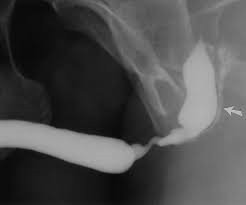

Initial Examination During your initial consultation, we will conduct routine blood and urine tests to evaluate kidney function, perform a urine culture, and complete a preoperative assessment. Additionally, a cystoscopy and a retrograde urethrogram (RGU) X-ray will be scheduled to precisely determine the location, length, and severity of the stricture. Dr. Raju R will take the time to address any questions or concerns you may have, thoroughly explaining the details, potential complications, and anticipated outcomes of the surgical procedure. Both the cystoscopy and RGU are brief, minimally uncomfortable procedures performed in our office.